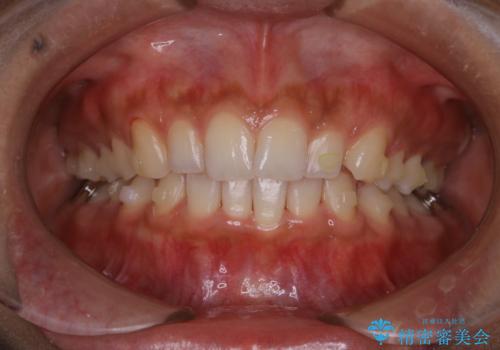

インビザラインでの矯正治療でアタッチメントset前のPMTC

担当医 歯科衛生士